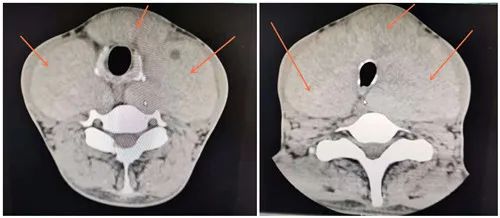

入院后經(jīng)過(guò)詳細(xì)檢查,發(fā)現(xiàn)情況比想象的更為復(fù)雜:劉先生的頸前可見(jiàn)腫塊隆起,越過(guò)胸鎖乳突肌后緣,對(duì)稱性,約28.0*14.0cm大小,CT顯示甲狀腺左右葉及峽部彌漫性腫大,腫物擠壓臨近氣管,使其受壓變窄,氣道狹窄,導(dǎo)致他呼吸困難。支纖鏡檢查發(fā)現(xiàn)氣管最狹窄處僅約4mm左右。